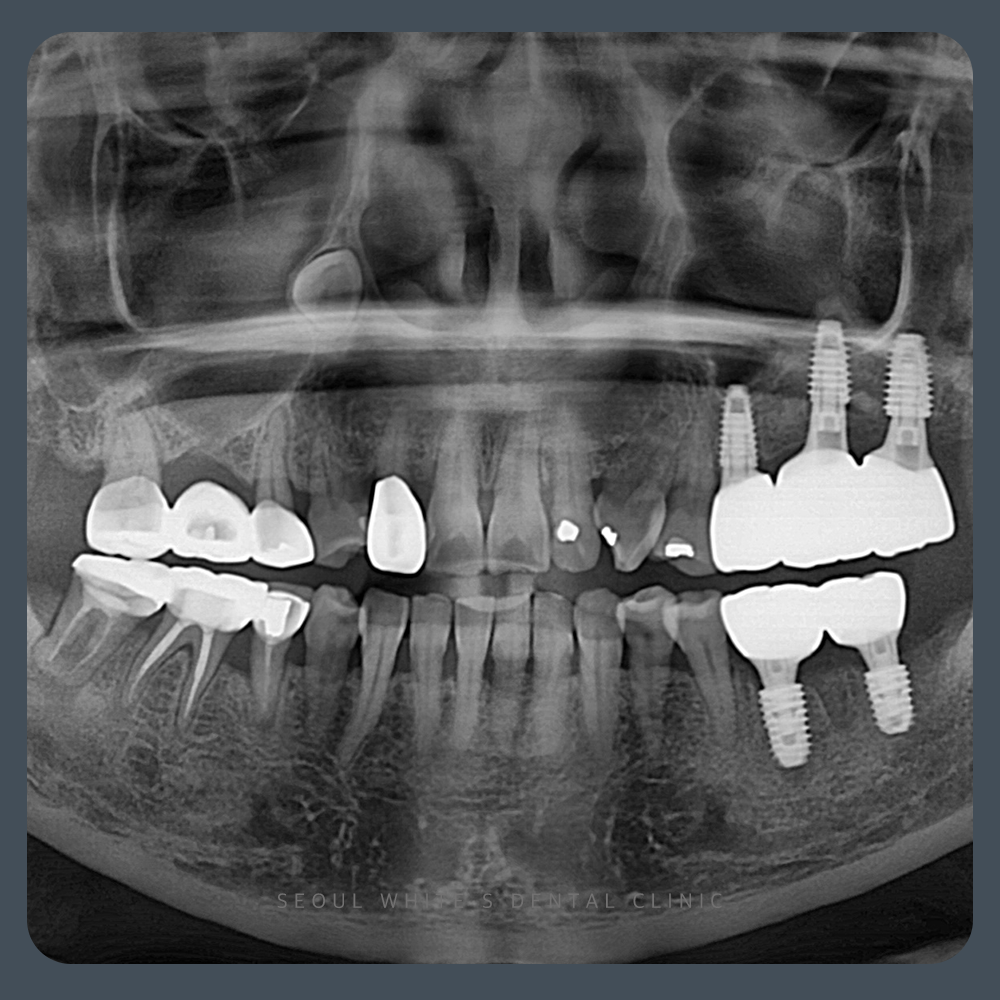

2025.01.23

술 후, 영도치과 임플란트 식립 위치가 확보되었고, 임플란트가 안정적으로 깊게 식립되었습니다. 회복 기간도 원활하게 진행되었으며, 결과적으로 자연스럽고 기능적인 임플란트가 완성되었습니다.